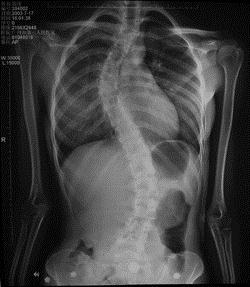

病历摘要: 患者××,女,17岁,发现剃刀背畸形3个月。查体:脊柱胸段向右侧凸,腰段向左侧凸,右胸廓呈剃刀背畸形,双下肢未见明显异常。为了明确诊断...

问题 病历摘要: 患者××,女,17岁,发现剃刀背畸形3个月。查体:脊柱胸段向右侧凸,腰段向左侧凸,右胸廓呈剃刀背畸形,双下肢未见明显异常。 为了明确诊断,该患者需哪些检查?

选项 A、胸腰椎MRI B、脊髓诱发电位 C、骨盆平片 D、肌电图 E、卧位Bend像 F、拍右侧手及腕部X线片 G、站立位摄脊柱前后位、侧位X线片